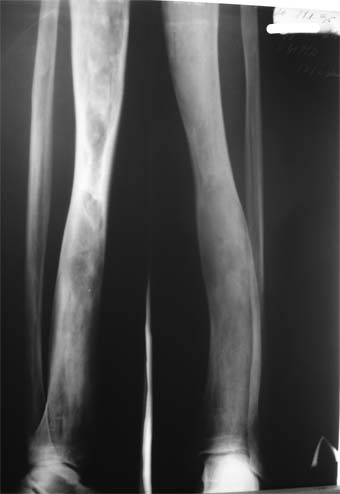

Коллеги!Пациент Д., 35 лет, В 1985 году был поставлен диагноз гемигипоплазия правой нижней конечности. Укорочение 5 см, в 1987 году остеотомия правого бедра, аппарат 4 месяца, удлинили на 2 см из-за нагноения спиц аппарат сняли. В настоящее время Жалобы на дискомфорт, тяжесть в левом бедре, голени при длительной ходьбе, при длительном лежании на левом бедре. Эти жалобы беспокоят втечение 5-6 лет. В 1999 году выявили "изменения" (со слов больного, выписки нет на руках) бедренной кости и костей голени слева. Тогда же предложили в ЦИТО срочно делать какую-то операцию. При осмотре: Правая нижняя конечность. Имеются рубцы на правом бедре по наружной и внутренней поверхностям. Ограничения движений в коленном суставе нет. Кровоснабжение, иннервация сохранены. Левая нижняя конечность. Левое бедро увеличено в объеме, при пальпации пальпируется бедренная кость большего диаметра по сравнению с левым бедром. Пальпация безболезненна. Голень обычной формы. Объем движений в суставах полный. Кровоснабжение, иннервация сохранены. Имеется разница в длине конечностей правая короче на 4-5 см за счет бедра и голени. В приложении вид больного и рентгенограммы бедра 2001 год и 2005 год. Что бы это могло быть? О чем можно думать? Онкология? С уважением Коробушкин Глеб Владимирович Российский государственный медицинский университет кафедра травматологии, ортопедии и ВПХ, доцент

В настоящее время имеется умеренный рубцовый процесс правого бедра не мешающий на объем движений в суставах. В коленном суставе слева бедро обычное, голень - булавовидное утолщение проксимального конца большеберцовой кости. На рентгенограммах тотальное поражение кости с увлечением в процесс проксимального эпиметафиза, поражение характерно для болезни Campanatsehi

У больного полиоссальноая форма фиброзной дисплазии с поражение левой бедренной и большеберцовой кости. На рентгенограммах - тотальное разрастание и остончение кортикального слоя. Имеется удлинение левой нижней конечности на 2,5-3 см за счет голени. Больному показано оперативное лечение левой большеберцовой кости.